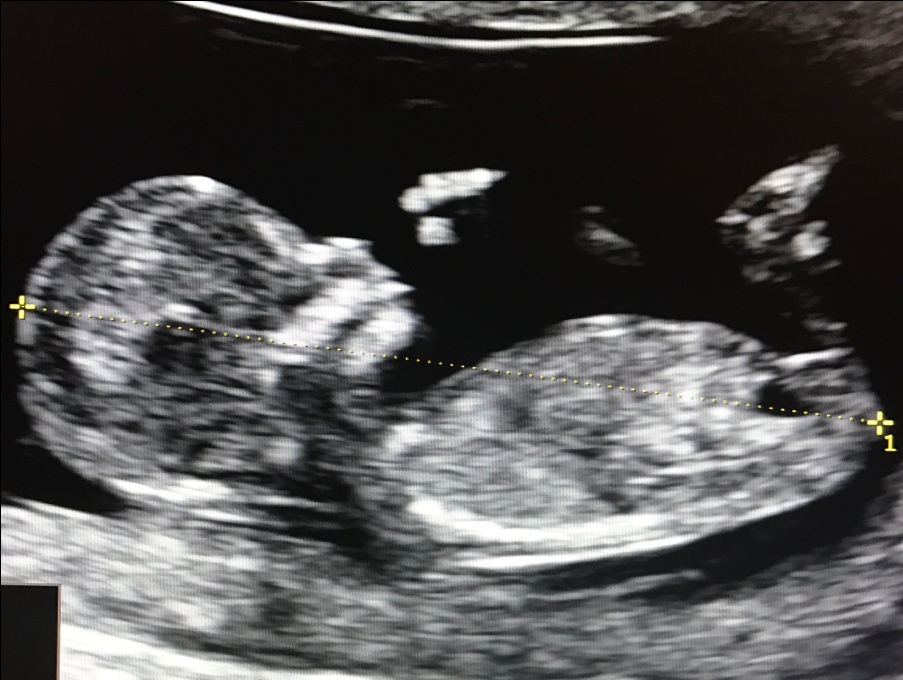

Правильное измерение КТР плода

Ручка плода Мозг плода в виде “бабочки” в норме